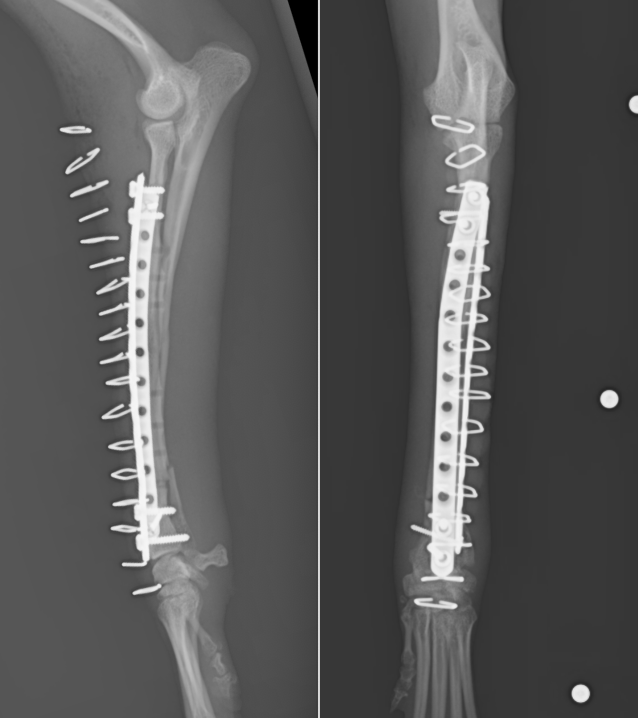

次の症例は11ヶ月のトイプードルで、スリングから飛び降りた後から足をケンケンするということで来院しました。左橈尺骨遠位斜骨折で、2日後に手術を実施しました。遠位骨折の場合尺骨(細い方の骨)には治療を行いませんが、骨折線も綺麗にあっているのがわかります。術後は次の日から足を着くことが可能で、1週間後に帰る時には通常に近い歩様で帰っていきました。その後1週間で抜糸となりますが、そこまでは散歩を5〜10分ほどにしてもらいます。ジャンプや激しい運動はしないでもらっています。その後2週間は散歩を15〜20分、その後1ヶ月は25〜30分で、その頃にプレートを1枚抜去します。

正面から見たレントゲン画像です。

横から見たレントゲン画像です。

術後のレントゲン画像です。足もまっすぐになり、尺骨という骨も綺麗にあっているのがわかります。